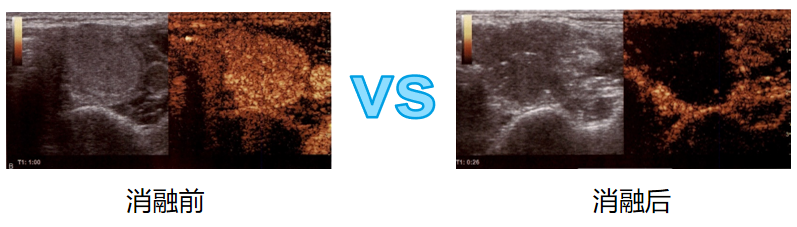

【造影技术】

使用造影剂后散射回声增强,明显提高超声诊断的分辨力,敏感性和特异性的技术。在甲状腺乳腺结节消融前、中、后的评估都起到了重要作用。消融前治疗规划:

※ 优于常规超声。

※ 准确反映甲状腺结节微循环灌注。

※ 设计最佳进针路线。

※ 分辨甲状腺和周围组织的结构关系。